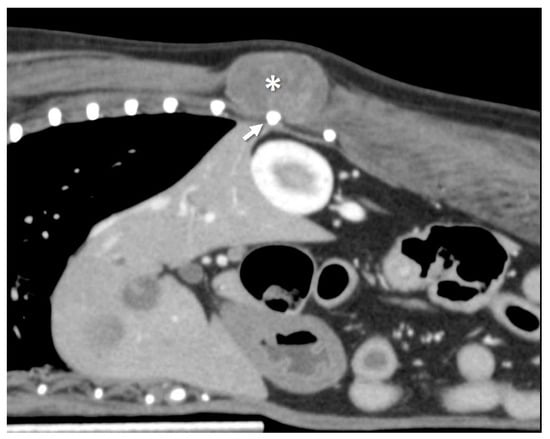

Figure 1.

Contrast-enhanced CT image, sagittal plane. The tumor is adjacent to the 12th rib. The dog was positioned ventrally, with the cranial side on the left side of the image. The * indicates the tumor; the arrow indicates the 12th rib.